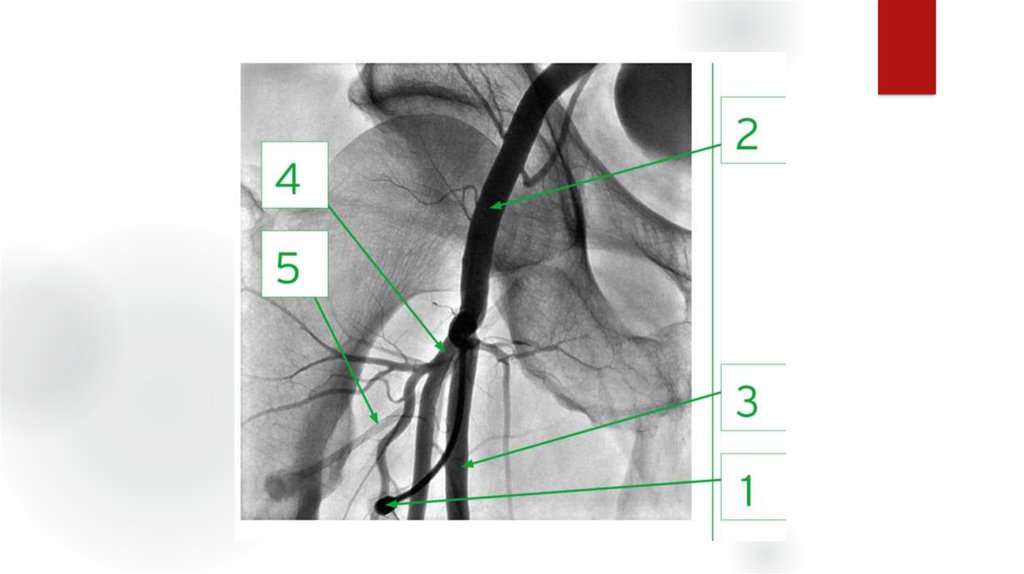

24. Оценка ангиограмм

Критерии:

- Окклюзии, их локализация

- Сегментарный уровень

- Степень

- Длинна пораженного участка

- Конфигурация и анатомия

- Количество пораженных артерий

- Морф.тип стеноза

- коллатеральное кровообращение